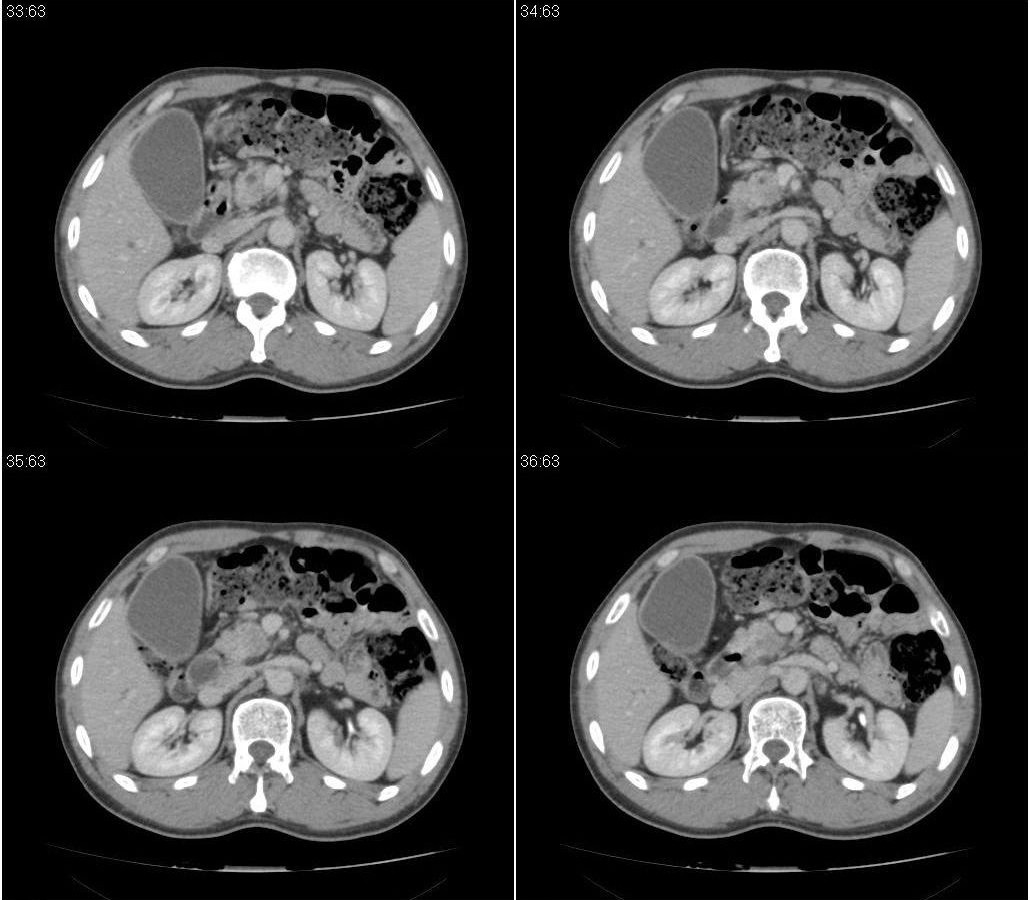

标题: CT21384:男性,50岁。发现无痛性黄疸十余天,B朝提示肝胆管 [打印本页]

标题: CT21384:男性,50岁。发现无痛性黄疸十余天,B朝提示肝胆管

1.考虑:壶腹占位病变(癌?)。

2.胆系低位梗阻:肝内外胆管扩张,胆囊增大,胰管扩张。

胰头癌伴低位胆道梗阻。

胆系低位梗阻(肝内外胆管扩张,胆囊增大,胰管扩张);考虑胰头癌或壶腹癌所致。

胰头强化欠均匀,胆胰管扩张。考虑胰头癌可能性大。

胆系低位梗阻(肝内外胆管扩张,胆囊增大,胰管扩张,钩突似有占位);考虑胰头癌